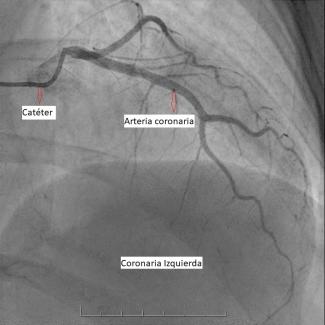

La sala donde te realizarán el estudio se encuentra a baja temperatura. Este procedimiento se efectúa con anestesia local y comienza con la introducción de un catéter por punción en una de las arterias de la muñeca o la ingle, de acuerdo a las características de cada persona.

Este catéter llega hasta las arterias coronarias y una vez allí se inyecta una sustancia de contraste, que permite visualizarlas y verificar si hay obstrucciones.

Mientras se inyecta la sustancia de contraste sentirás calor, esto es normal. Asimismo, en determinados momentos el/la médico/a te solicitará que inspires profundamente, retengas el aire y no te muevas. Es muy importante que permanezcas lo más quieto/a posible durante el procedimiento.